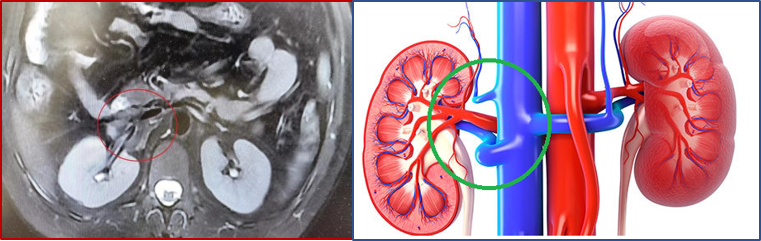

患者肖女士,33岁,两个月前出现腰背部间断性疼痛,起初并未重视,休息多日后不但没有好转,反而疼痛加剧,遂来独墅湖医院就诊。经磁共振检查,发现患者腹腔深部长了一个“鸭蛋”大小肿物,而且这个肿瘤生长在“肾门”部位。这个部位就好比是高架上的立交桥,是肾脏血管和输尿管出入的关键部位,更危险的是,片子上看肿瘤与血管基本没有界限。

在征得肖女士本人及家属的意见后,2月20日,麻醉科李健、侯永恒两位主任负责麻醉,血管外科团队张喜成主任协同黄献琛、孙元及李观强三位医生开始手术。术中发现肿瘤果然完全包绕大中血管,下腔静脉、肾动脉和肾静脉均从肿瘤中间穿过,而且粘得很紧没有明显界限,有时甚至需用刀尖将瘤子从血管上“剔、削”下来。经过4个半小时的努力,医生团队终于将肿瘤完整地剥除下来,同时保护了患者的肾脏和血管,做到术中未输血。术后血管外科与介入科护士严格监管、精心护理,最终在医护团队共同努力下,肖女士顺利康复,未发生任何并发症。

血管外科与介入科张喜成主任介绍,腹膜后肿瘤通常发生在人体的腹膜后腔空隙中,由于腹膜后空间较大,肿瘤刚开始大部分患者无明显症状,随肿瘤发展越来越大,患者会逐渐出现一些组织的压迫症状,如:腰背部胀痛、腹胀、尿频、肾积水等。本次手术患者的肿瘤是节细胞神经瘤,又称神经节细胞瘤,是一类罕见的起源于交感神经节原始嵴细胞的良性神经源性肿瘤,早期患者一般无任何症状,术前确诊率低,但随着瘤体增大,少数患者可表现为局部不适或疼痛。腹膜后的神经节细胞瘤大部分会挤压血管,将血管挤到一边,手术相对易于分离,但像肖女士这样的肿瘤完全包绕了血管、而且生长坚韧、与血管紧密粘连无界限的很少见。